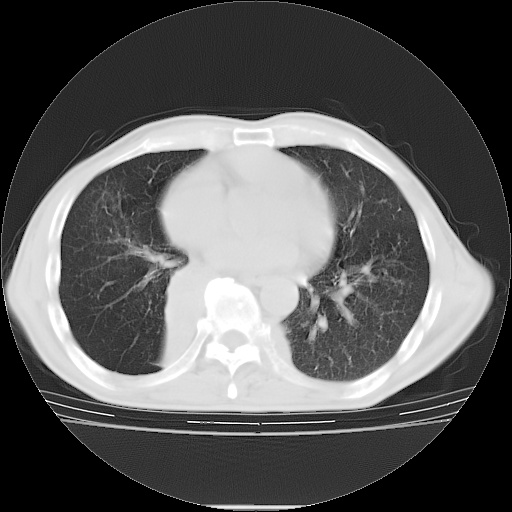

男性患者,63岁。右侧胸背部疼痛2月,加重一周。

还有纵隔多处肿大淋巴结及肋骨的改变、两肺多发结节灶。

右肺下叶支气管狭窄闭塞,右下肺不张,气管前间隙淋巴结肿大,两上肺散在分部粟粒灶,沿肺血管支气管束分部,血管支气管束走形较为光滑。考虑右肺中心型肺癌合并肺不张,纵隔淋巴结转移,两上肺癌性淋巴管炎

1)右肺下叶中心性肺癌并纵隔淋巴结转移,两肺转移,左侧肋骨转移。2)双肺上叶继发性结核。

右肺下叶中心性肺癌并纵隔淋巴结及两肺、左侧肋骨转移。双肺上叶继发性结核表现。